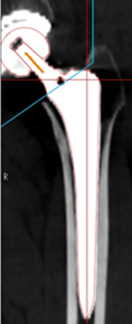

②術前計画機能を用いた術後ROM sim

![]() |

| 図1: デジタイズ後骨モデルを作成 | 図2: ハレーション修正(上段:修正前 下段:修正後) | 図3: 使用インプラントCADデータをマッチング |

設置角度精度

| 本研究 | cf: non-HC used | |

|---|---|---|

| RI | 3.4±2.6(0~13) | 6.2±6.4(0~34.4) |

| RA | 3.2±2.5(0~15) | 8.3±6.2(0.1~24) |

| SA | 8.2±6.5(0~36) | 9.3±7.4(0~36.3) |

インピンジメント角度

| 平均±標準偏差 | 最小~最大 | |

| 屈曲 | 118±6 | 66~120 |

| 伸展 | 29±4 | 4~30 |

|

*80度以下の2症例 大腿切骨部と寛骨側巨大骨棘及びAIISとのB-B imp |

☆15度以下の4症例 小転子と坐骨との生理的部位でのB-B imp |